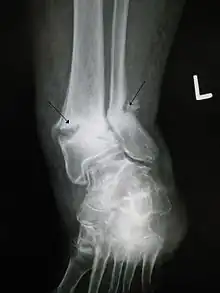

Une fracture ancienne avec pseudarthrose des fragments de fracture.

Le mécanisme de l'ostéogenèse n'est pas clair. La thérapie PEMF revendique un certain avantage dans le traitement des fractures, mais avec des preuves issues d'essais randomisés « insuffisantes pour conclure à un bénéfice de la stimulation de la croissance osseuse » dans la pratique clinique actuelle du traitement des pseudarthroses et fractures aiguës[1]. Une revue systématique et méta-analyse récente suggèrent néanmoins que « PEMF ou LIPUS peuvent être bénéfiques dans le traitement des fractures aiguës (subissant un traitement non opératoire et les fractures aiguës du membre supérieur) en ce qui concerne le temps de consolidation radiologique et clinique »[1]. Une stimulation de la croissance osseuse PEMF ou LIPUS accélère aussi la consolidation de fractures diaphysaires aiguës[1].